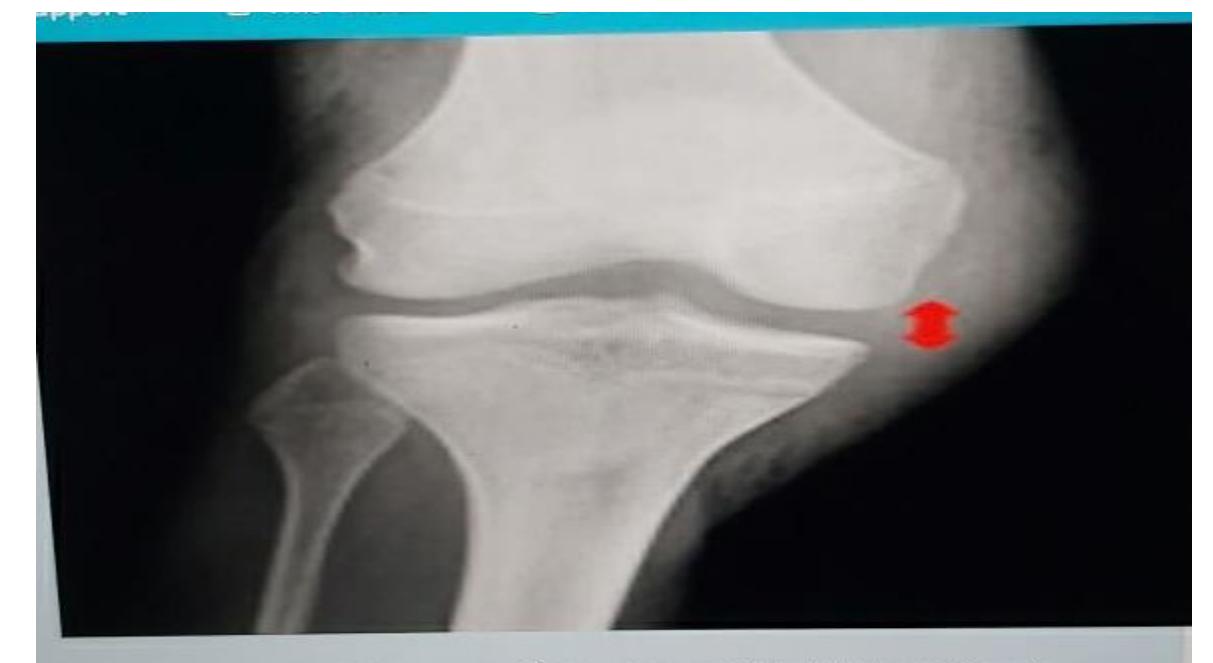

Q8/ What is the type of fracture shown in these pictures?

- A- Salter harris fracture II